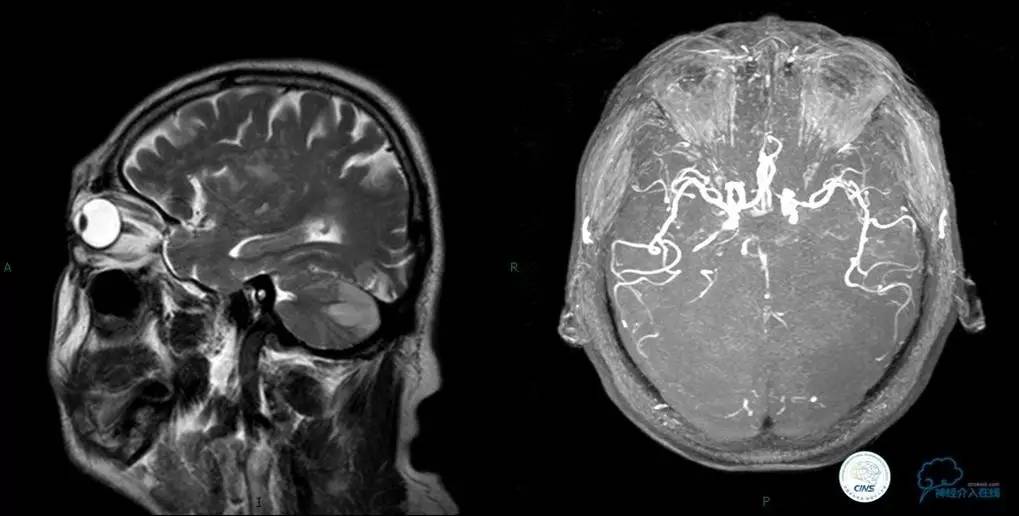

▼头颅MR

▼入院MR

▼术前DSA